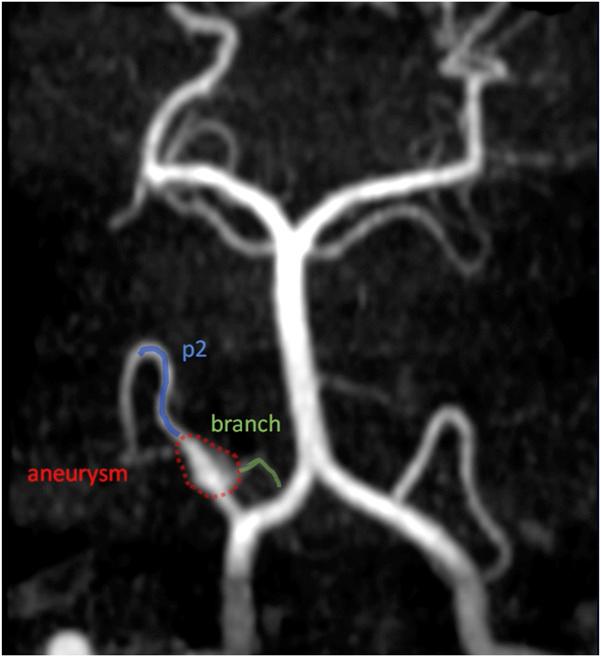

The patient underwent a right far-lateral craniotomy with excision of the dolichoectatic right PICA aneurysm with an additional outflow branch. An end-to-end reanastomosis was performed from the proximal PICA to the larger distal outflow PICA vessel, followed by an end-to-side anastomosis of the second outflow branch to the distal PICA; a salvage bypass with side-to-side V4-p2 reimplantation was later conducted because of thrombus formation at the initial end-to-end reanastomosis.

患者接受了右侧远外侧开颅手术,切除了带有一个额外流出分支的梭形扩张型右侧PICA动脉瘤。对近端PICA与较大的远端流出PICA血管进行了端端再吻合,随后将第二个流出分支与远端PICA进行了端侧吻合;由于最初的端端再吻合处形成血栓,后来进行了V4 - p2侧侧再植入的挽救性旁路手术。